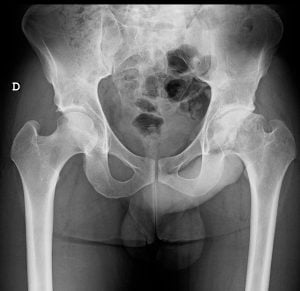

• Artrose da Anca / Coxartrose

Coxartrose ou Artrose da Anca (a mais comum)

• Osteonecrose (Necrose Avascular da Cabeça Femoral – NAV)

As principais razões para esta intervenção são as patologias da anca, causadoras de desgaste articular (artrose da anca) e consequentemente, dor, rigidez, deformidade, encurtamento do membro inferior e claudicação.